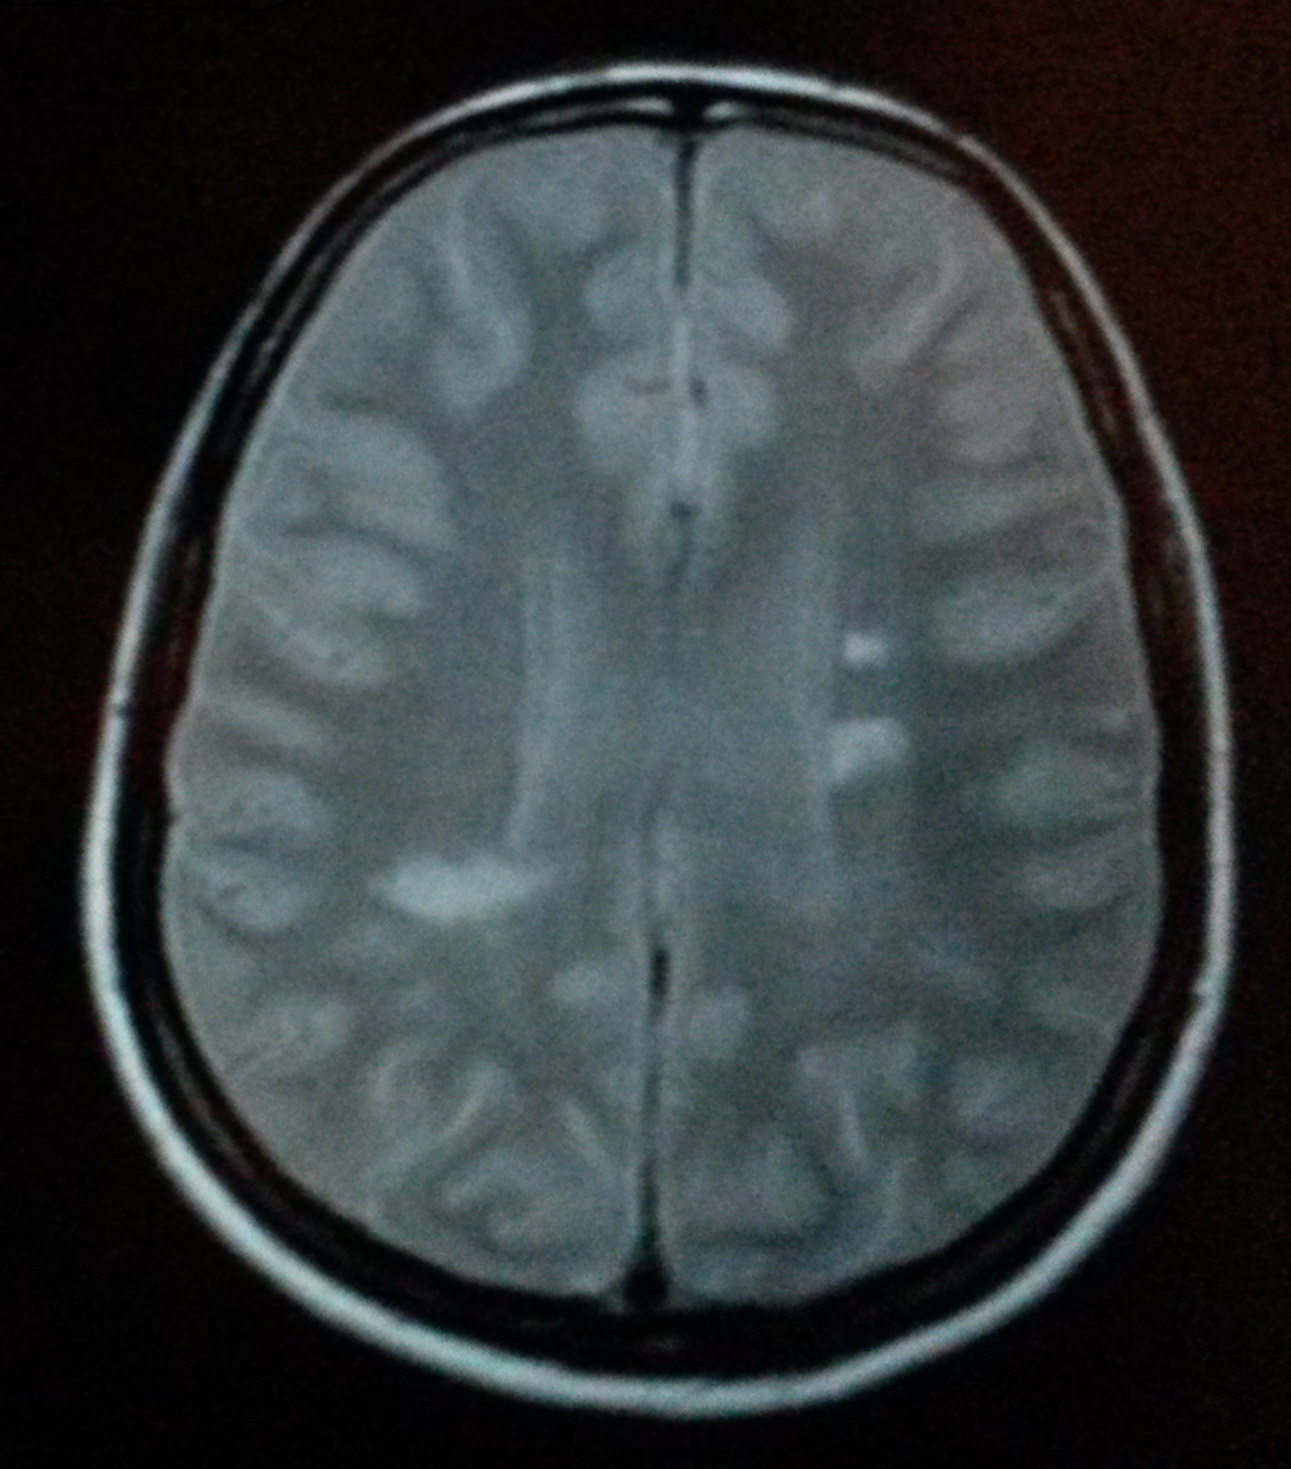

Hjelpes!!! Gurimalla, ka e d her tenkte e, rene halloween :-O I ren panikk måtte e se nærmere på de andre bildene, for MR bilder e har sett av Plakk (hvite flekker) og forklart hva MS egentlig er, ser slik ut:

Bildet som var litt mer interessant å se på var bilde med kontrastvesken. Det ser jo ut til at alt funker som det skal?